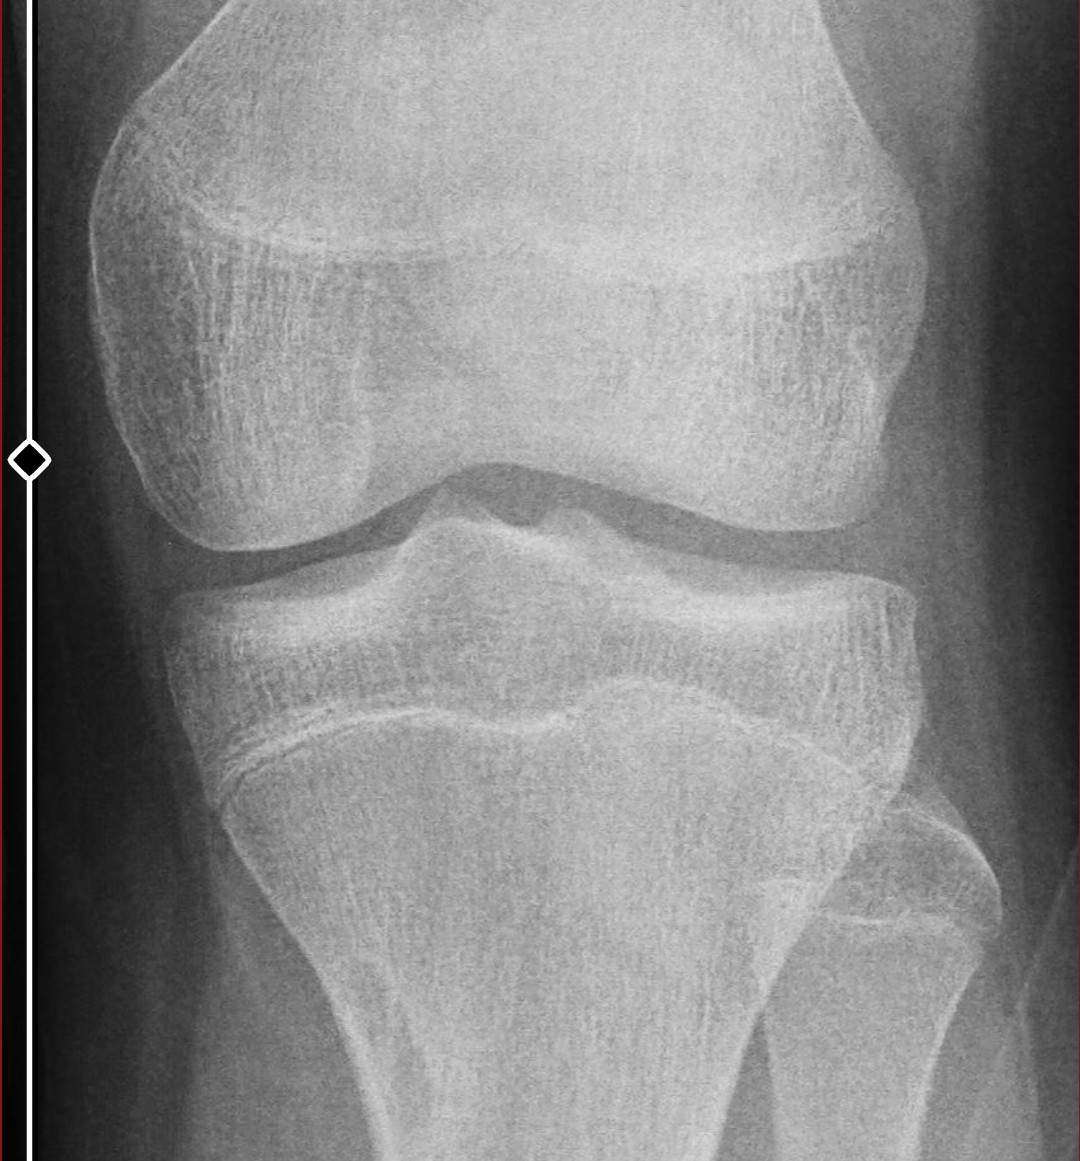

6 ayda kemiklerim 1-1.5 sene yaşlanmış. kemik yaşım kronolojik yaşıma eşit.

tahmin edilen yetişkin boyum 179-181 arasında

yine de dizi bırakayım buraya dizden çok anlamıyorum belki hala 3 cm uzama mümkündür